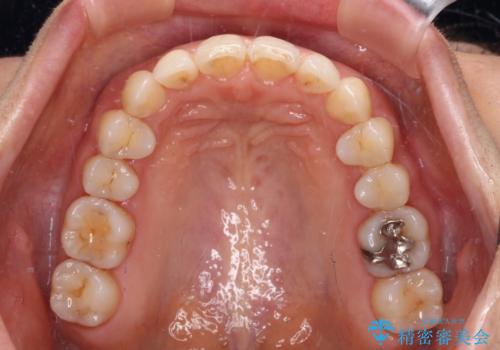

- 矯正治療の後戻りを気にして来院された患者様です。

後戻りは軽微であったので、インビザライン・ライトにより矯正治療を行うこととしました。